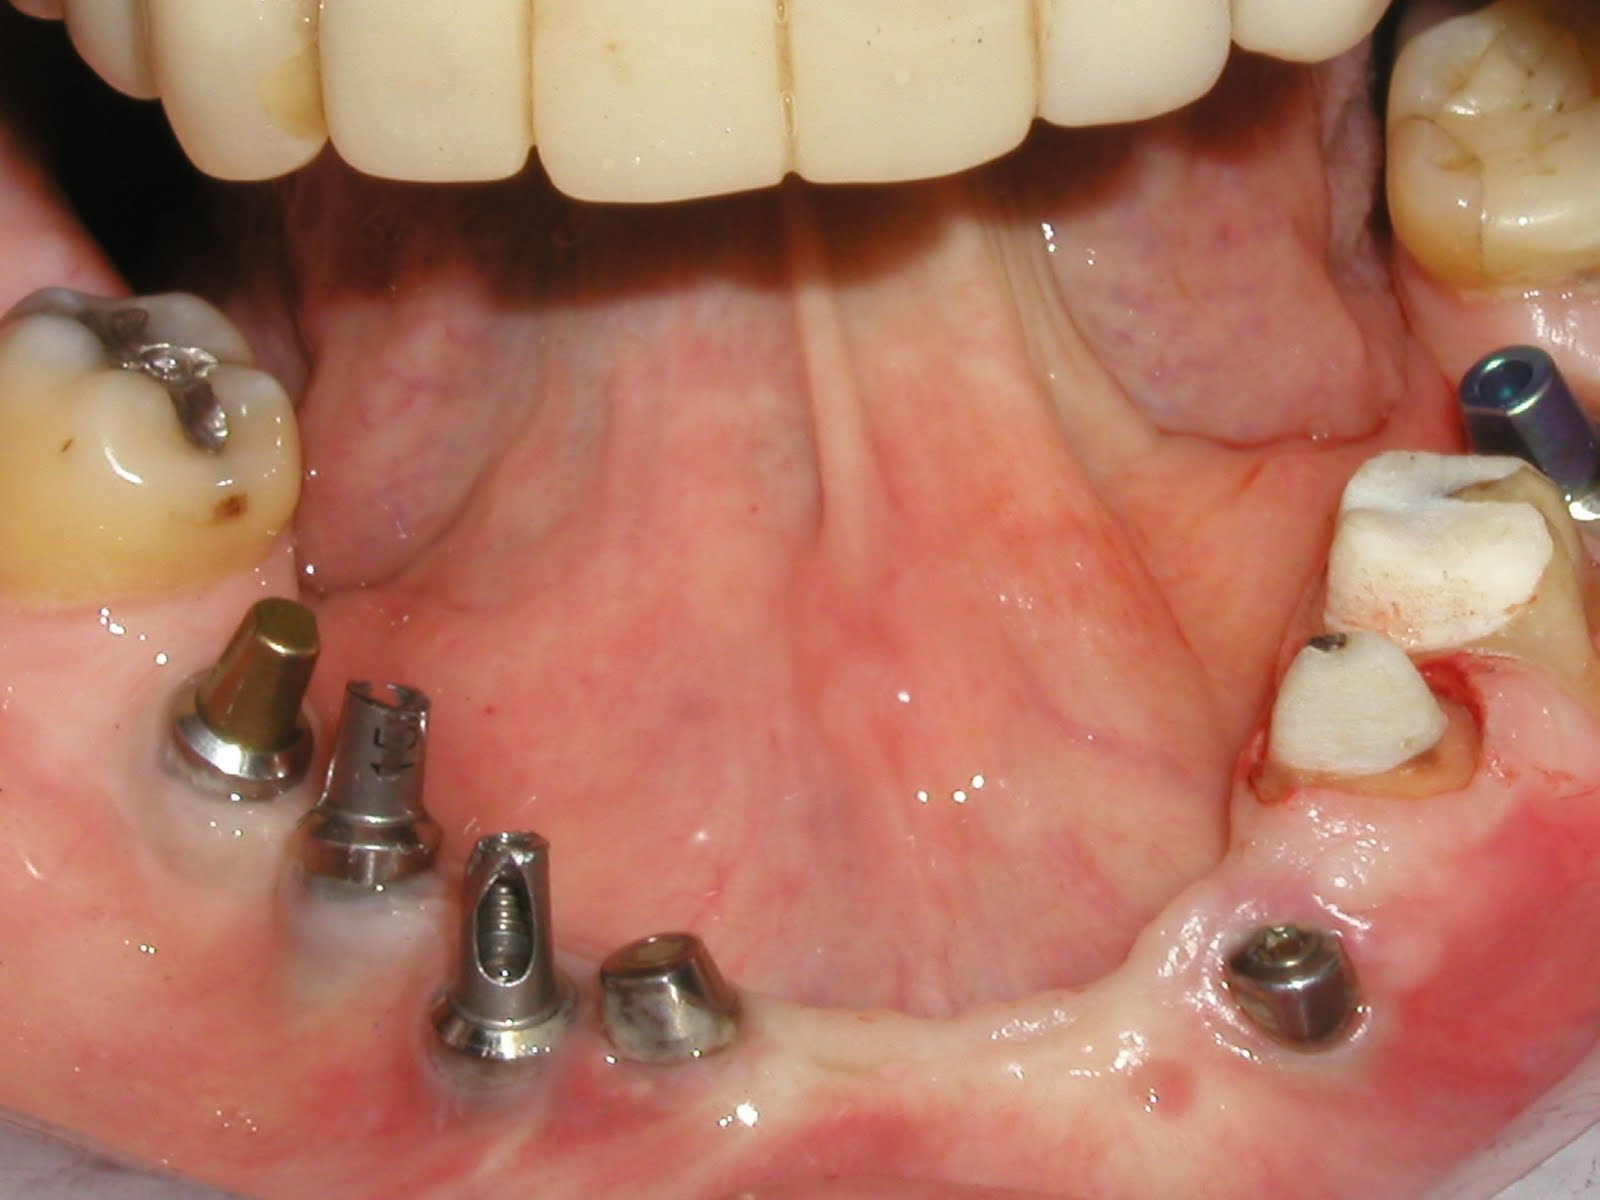

What I am talking about is showing them. Take before and afters, and show them how crappy it looked before and how awesome it looks now. Dust off your intra oral camera and show them your hard work.

Before internal bleaching

After internal bleaching.

Before internal bleaching and a new filling

After internal bleaching and a new filling.I get so many WOWs. People are impressed. Occasionally, some one will ask if I can do that to some of their other teeth. And, well, it is good for my ego.